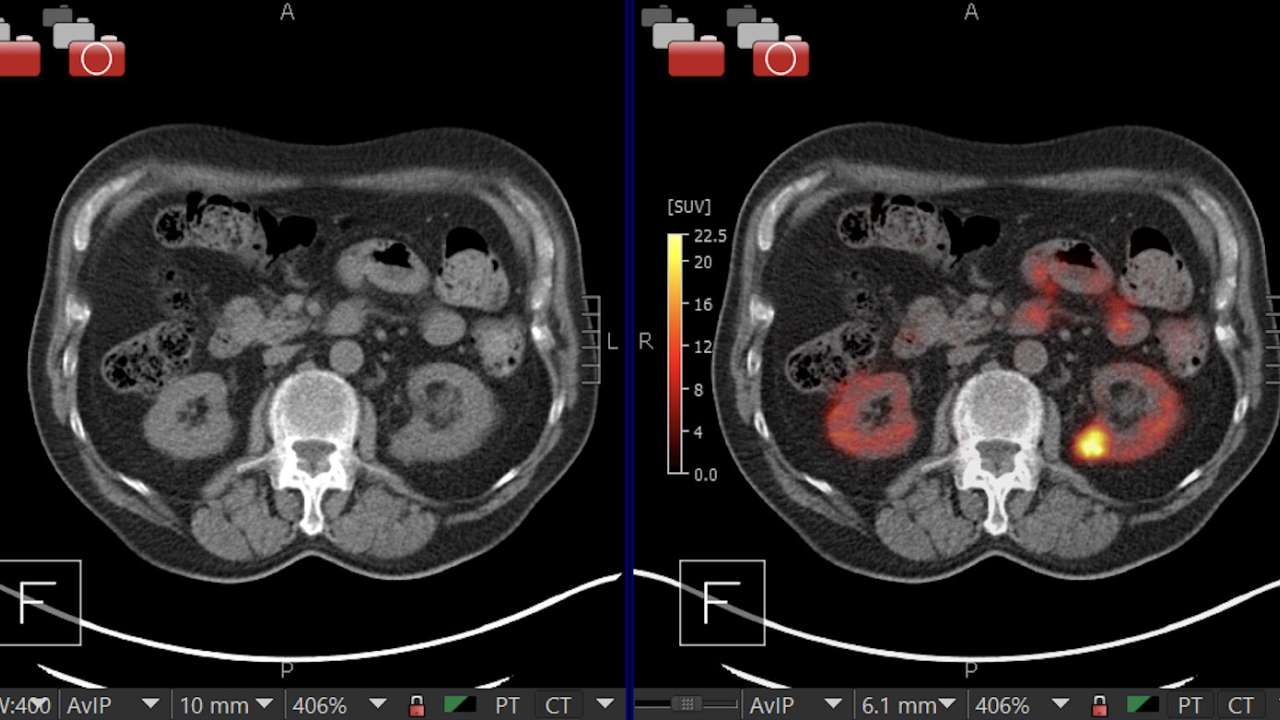

Dive into the stunning world of abstract Renal Cancer Pet/ct with vast arrays of imaginative images. highlighting the innovative use of photography, images, and pictures. ideal for modern art and design. Browse our premium Renal Cancer Pet/ct gallery featuring professionally curated photographs. Suitable for various applications including web design, social media, personal projects, and digital content creation All Renal Cancer Pet/ct images are available in high resolution with professional-grade quality, optimized for both digital and print applications, and include comprehensive metadata for easy organization and usage. Our Renal Cancer Pet/ct gallery offers diverse visual resources to bring your ideas to life. Time-saving browsing features help users locate ideal Renal Cancer Pet/ct images quickly. Reliable customer support ensures smooth experience throughout the Renal Cancer Pet/ct selection process. Cost-effective licensing makes professional Renal Cancer Pet/ct photography accessible to all budgets. Professional licensing options accommodate both commercial and educational usage requirements. Diverse style options within the Renal Cancer Pet/ct collection suit various aesthetic preferences. The Renal Cancer Pet/ct collection represents years of careful curation and professional standards. Each image in our Renal Cancer Pet/ct gallery undergoes rigorous quality assessment before inclusion. Multiple resolution options ensure optimal performance across different platforms and applications.